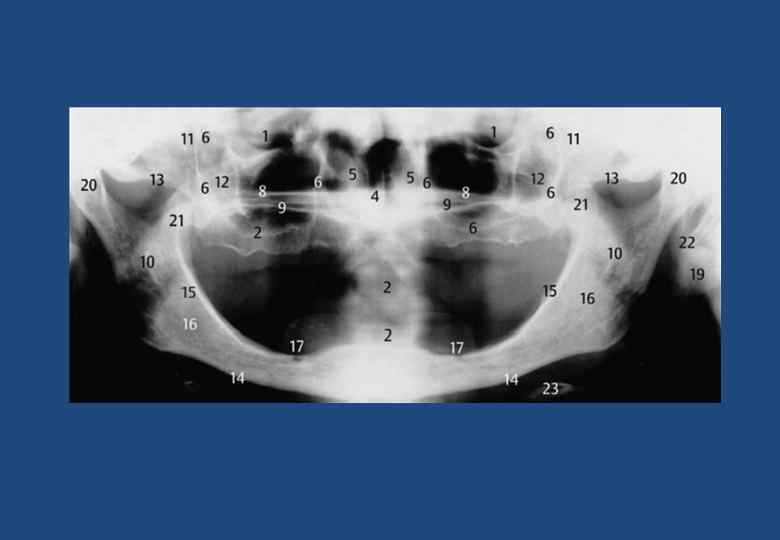

• • • • • • • 1. Верхнечелюстная пазуха границы 2. Горизонтальная пластинка небной кости и латеробазальная граница полости носа 3. Венечный отросток, наслаивающейся на крыловидный отросток клиновидной кости, бугор верхней челюсти и мягкие ткани небной занавески 4. Тело скуловой кости с безымянной линией 5. Безымянная линия (линия на височной поверхности скуловой кости) 6. Скуловая дуга 7. Височно-скуловой шов 8. Суставная ямка 9. Суставной бугорок 10. Мягкие ткани ушной раковины 11. Наружный слуховой проход 12. Мыщелковый отросток и головка нижней челюсти 13. Шиловидный отросток височной кости 14. Верхние отделы глотки 15. Небная занавеска 16. Спинка языка 17. Отверстие нижнечелюстного канала 18. Нижнечелюстной канал 19. Передний бугорок первого шейного позвонка 20. Зуб второго шейного позвонка 21. Отверстие поперечного отростка второго шейного позвонка 22. Наружная косая линия (продолжение переднего края в каудальном и боковом направлениях) 23. Височный гребень 24. Бугор верхней челюсти 25. Крыловидно-небная ямка